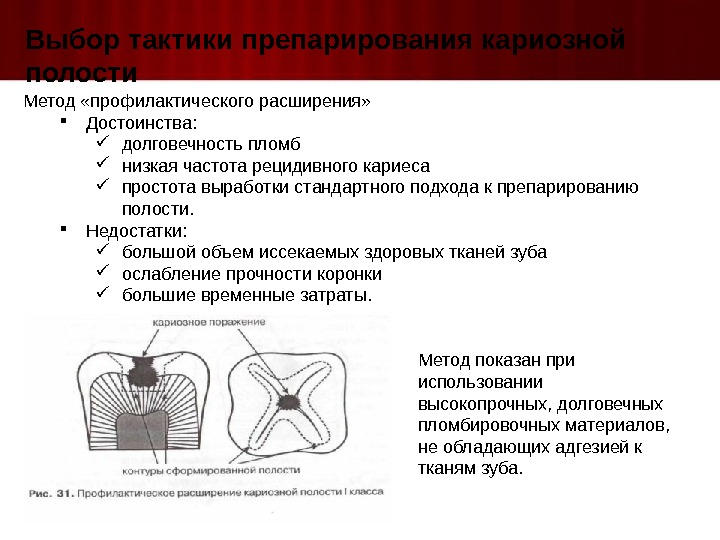

Препарирование кариозных полостей III класса: пошаговое руководство с фото